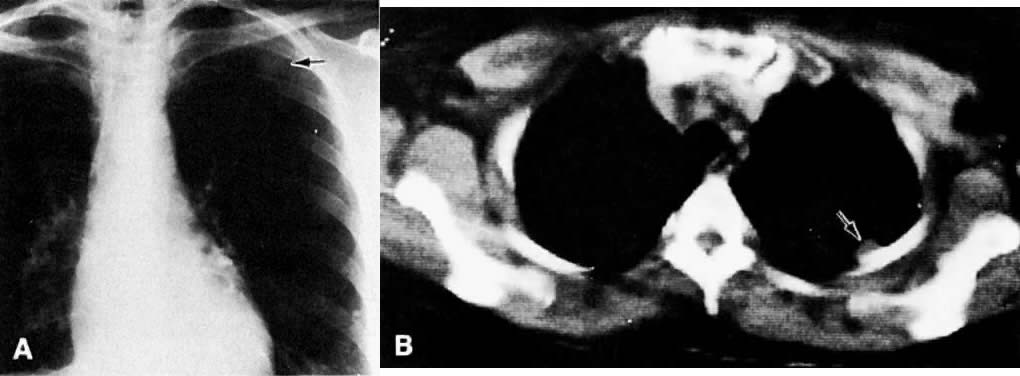

Chest CT is a more sensitive and accurate test that can be used to confirm the presence of lesions and to differentiate benign from malignant ones. CT better visualizes lesions in the apices of the lungs, costophrenic sinuses, cardiophrenic angles, mediastinum, and supradiaphragmatic areas. In some cases, pleural-based lesions (Fig. 53) and loss of rib detail are also better demonstrated by CT.137 CT can identify diffuse calcification by assigning a higher number to the nodule. Unfortunately, CT cannot differentiate benign from malignant nodules when they are not calcified. Recent advances in CT technology, including spiral CT, have been used to reconstruct three-dimensional images of the chest and detect tumor spread to the pleura. In addition, spiral CT probably has a higher rate of detection of metastatic nodules than conventional CT, because of the lack of respiratory motion artifacts. CT-guided fine-needle percutaneous aspiration biopsy is used to differentiate benign from malignant chest nodules with a high degree of accuracy.

Fig. 53. A. Posteroanterior chest film with metastatic lesion in left upper lung field, second anterior interspace ( arrow ). B. Axial CT scan shows the lesion ( arrow) projecting from the pleura.